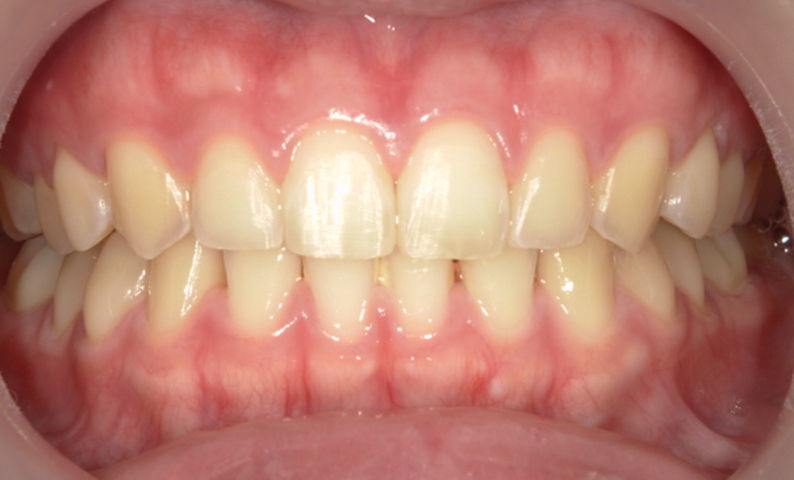

| 治療前 | 治療後 |

|---|---|

|